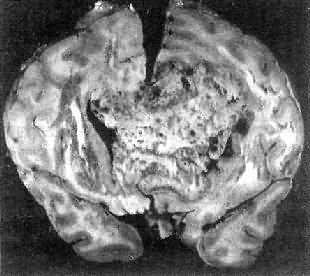

一、中枢神经肿瘤(一)胶质瘤 胶质瘤(glioma)具有特异的不同于其它部位肿瘤的生物学特性: (1)良恶性的相对性:无论高度分化或低度分化的胶质瘤均呈浸润性生长,更无包膜形成。生长迅速、间变程度高的肿瘤,与周围组织截然不同,故边界往往较清楚。 第三脑室分化良好的幼年型星形胶质细胞瘤,由于位于手术禁区,无法进行切除。因此预后不佳。 (2)局部浸润:胶质瘤的浸润性生长主要累及血管周围间隙、软脑膜、室管膜、神经纤维束间。 (3)转移:①脑脊液转移是颅内肿瘤常见的转移方式,相当于颅外恶性肿瘤细胞的淋巴道浸润和转移,特别是位于脑室旁、脑池旁的肿瘤发生这种转移的机会更多。②颅外转移极少见,其中80%以上均有颅脑外科手术史。 1.星形胶质细胞瘤(astrocytoma) 本瘤约占颅内肿瘤的30%,占神经胶质瘤的70%以上。男性较多见。最近研究表明该肿瘤中原癌基因sis有过度表达,erb-B1则有放大。 肉眼观,肿瘤为数厘米的结节至巨大块状。分化较好的肿瘤,境界不清;而分化程度较低的肿瘤则境界分明。瘤体灰白色。质地视肿瘤内胶质纤维多少而异,或硬、或软、或呈胶冻状外观,并可形成大小不等的囊腔。由于肿瘤的生长、占位和邻近脑细胞的肿胀,脑的原有结构因受挤压而扭曲变形(图16-23)。

图16-23 星形胶质细胞瘤 左大脑半球肿胀,肿瘤边界不清,部分呈胶冻状 镜下,肿瘤细胞形态多样,可相似于纤维型星形胶质细胞、原浆型星形胶质细胞和肥胖星形胶质细胞,故分别称为纤维型、原浆型和肥胖型星形胶质细胞瘤。前二者为良性肿瘤,后者性质介于良恶性之间。如肿瘤细胞出现间变,细胞密度增大,异型性明显,核深染,出现核分裂像,毛细血管内皮细胞增生,则为间变性星形胶质细胞瘤,为恶性肿瘤。 高度恶性的星形胶质细胞瘤称为多形性胶质母细胞瘤(glioblastoma multiforme),多见于成人。肿瘤好发于额叶、颞叶白质,浸润范围广,常可穿过胼胝体到对侧,呈蝴蝶状生长(图16-24)。瘤体因常有出血坏死而呈红褐色。镜下,细胞密集,异型性明显,可见怪异的单核或多核瘤巨细胞。出血坏死明显,是其区别于间变性星形胶质细胞瘤的特征。毛细血管明显增生,内皮细胞增生、肿大,可导致管腔闭塞和血栓形成。肿瘤发展迅速,预后极差,患者多在2年内死亡。